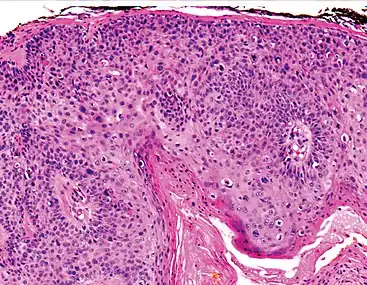

Bowen's disease is essentially equivalent to and used interchangeably with cSCC in situ, when not having invaded through the basement membrane.[12] Depending on source, it is classified as precancerous[13] or cSCC in situ (technically cancerous but non-invasive).[47][48] In cSCC in situ (Bowen's disease), atypical squamous cells proliferate through the whole thickness of the epidermis.[12] The entire tumor is confined to the epidermis and does not invade into the dermis.[12] The cells are often highly atypical under the microscope, and may in fact look more unusual than the cells of some invasive squamous-cell carcinomas.[12]

cSCC in situ, high magnification, demonstrating an intact basement membrane.[12]

In invasive cSCC, tumor cells infiltrate through the basement membrane. The infiltrate can be somewhat difficult to detect in the early stages of invasion: however, additional indicators such as full thickness epidermal atypia and the involvement of hair follicles can be used to facilitate the diagnosis. Later stages of invasion are characterized by the formation of nests of atypical tumor cells in the dermis, often with a corresponding inflammatory infiltrate.[12]